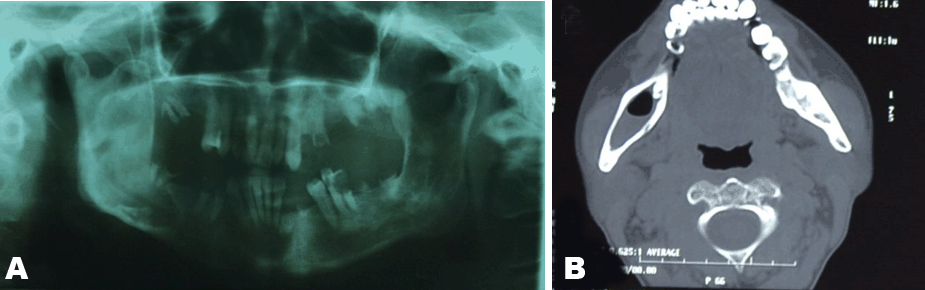

A palpable right mandibular mass was noted and panorex radiograph and computerized tomography (CT) scan were done. It was diagnosed as a right mandibular cyst (Figure 2).

Figure 2:(A and B) (Left) Panorex Radiograph, and (Right) CT scan showing a right mandibular cyst.